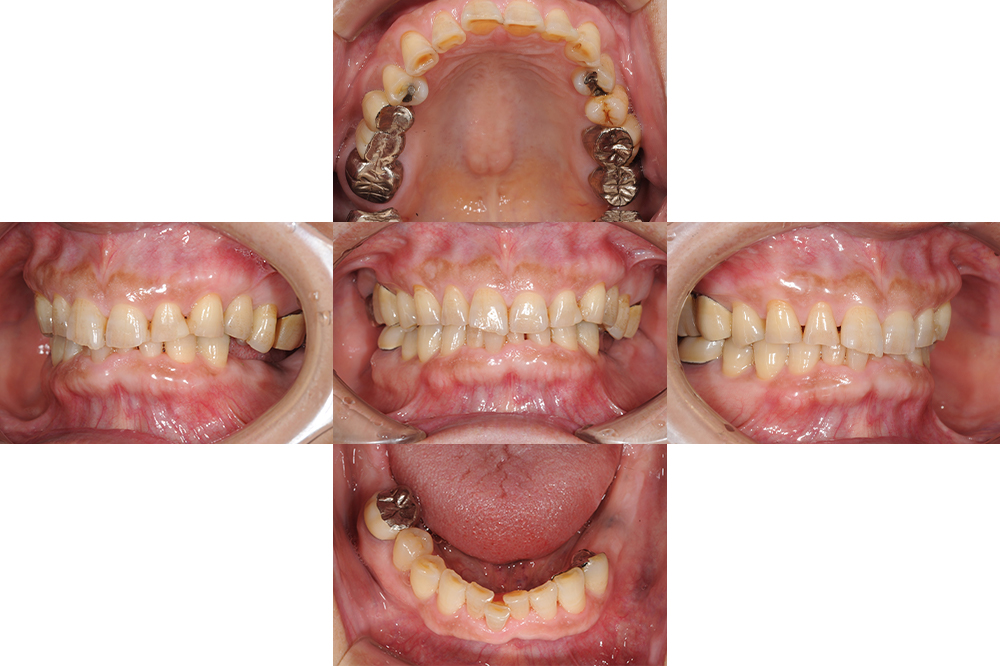

年齢 71歳 性別 女性 初診日 主訴 前歯が欠けた 治療内容 ・インプラント ・セラミック修復 治療期間 9ヶ月 治療費用 250万円 治療経過 全体的に歯が磨耗し、下顎奥歯には義歯が装着されていたが義歯は破損し使えていない状態であった。 今回奥歯でしっかり咬め…